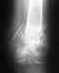

Добрый день, моя мама 55 лет жалуется на боль в косточке стопы. Сделали рентген. Запись к врачу через неделю (сельская местность) помоготи с расшифровкой рентгена. Заранее благодарен!

• Кликните для загрузки файла unnamed.jpg